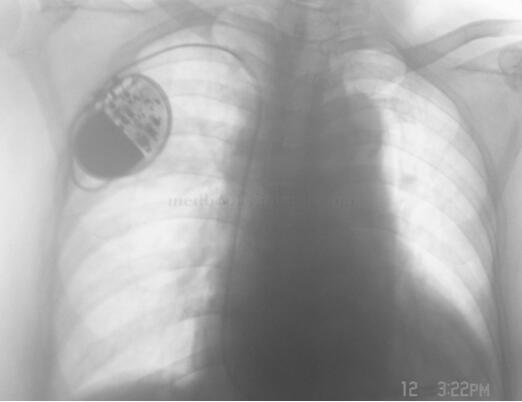

入院经抗感染(克林霉素+阿莫西林/舒巴坦)治疗3日,症状无好转,体温 39.2~40℃,白细胞 24.4×109/L,中性粒细胞 92.2%,改用亚胺培南(0.5g,q8h.)治疗,体温一度降至正常。4日后体温再次上升至39℃以上,血培养仍为阴沟肠杆菌。考虑患者发热与心腔内废弃电极有关,请心内科拔除电极(图9-3-2),拔除的电极头端有颗粒状赘生物,取之培养出阴沟肠杆菌。拔除电极的次日体温即下降,之后2周体温在37.6℃以内(仍使用亚胺培南),3次血培养均阴性,白细胞 5.7×109/L。随后的1个月继续使用亚胺培南,但患者每数日发生一次38.5℃左右的体温波动,期间白细胞正常,连续9次血培养均阴性。

图9-3-2 拔除心腔内废弃电极后的胸片